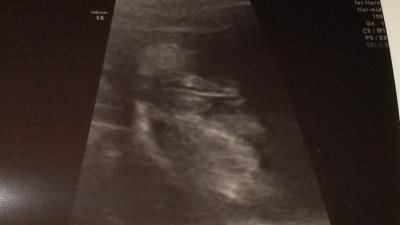

Hallo ihr lieben. Könnt ihr was erkennen oder habt ihr åhnliche bilder? Lieben dank die landmotte

Hallo Monatsgenossin Ich meine da einen Piepmatz zu erkennen. Was meinte der Arzt? LG Antje

PENIIIIIIIIIIIIIIIIIIIIIIIIS

Als mein Sohn gerade an meinem Laptop vorbeigelaufen ist und ein Blick mit auf das Ultraschallbild geworfen hat, fragte er ob das ein Bild von einem kleinen Elefanten wäre. Tut mir leid, ich kann auf dem Bild gar nichts erkennen. Aus welcher Sicht ist das aufgenommen und was genau sieht man auf dem Bild? Gruß Sylvia

links der Popo und... wie drücke ich es nun aus... von unten auf die Hoden fotografiert

Hodensack mit Penis. Dieser Strich ist die "Wchstumsnaht" die jeder Mann unten zwischen beiden Hoden und den Penisschaft hoch haben. So würde ich es interpretieren.

Mh doc sagt eindeutig schamlippen

Ich hätte auch auf ein Mädchen getippt. Bei meinen Jungs war der Penisse eindeutiger. Das hier ist doch eher ein Brötchen....

ich sehe keine 3 Striche?! vlt ist aber auch das Foto nicht so deutlich wie in echt

Hi, Das sieht nach Mädchen aus. Liebe Grüße

3 striche Mädchen